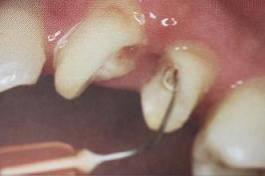

纤维桩粘接时应使用根管专用的微型毛刷。形态和桩道吻合,毛刷头部可弯曲,以达到较深的根管底端,有利于粘接剂的均匀涂布。

采用纳米级毛刷,根管涂擦后可较好的提高粘接效果。

根管内涂抹粘接剂时,理想的粘接剂层厚度为25um - 40um,厚度增加或不均匀不利于纤维桩的顺畅就位,多余的粘接剂的存在会加速树脂水门汀的固化速度。

根管内涂抹粘接剂的较规范操作应是:毛刷蘸取粘接剂在根管内反复涂擦20s,涂抹2-3层,然后用纸尖吸取干净,气枪吹5s使粘接剂中的溶剂快速挥发。此操作中,大锥度吸潮纸尖非常关键,它不仅可以吸取多余的粘接剂,同时也可使粘接剂在根管内铺展均匀。医生朋友不要“忽视小物件铸成大事件。